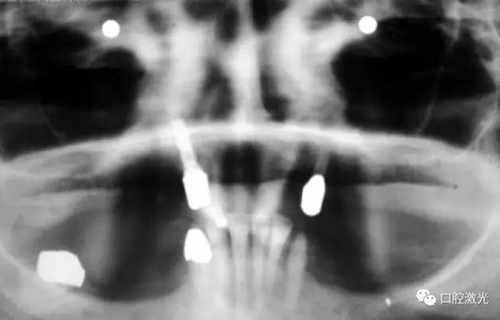

如今,種植體周圍炎的治療完成已經(jīng)過(guò)去了10多年,上顎義齒的狀況沒(méi)有再出現(xiàn)問(wèn)題。種植體周圍組織基本健康。

治療十年以上恢復(fù)情況

如果不及時(shí)治療,種植體周圍炎會(huì)導(dǎo)致種植體失敗。在本例中,種植體的缺失將給患者的生活帶來(lái)嚴(yán)重的不便。得益于激光對(duì)種植體周圍病變組織的殺菌治療,使得發(fā)炎組織得到有效控制,同時(shí)使得周圍軟、硬組織得到了很好的保持和很快的恢復(fù)。